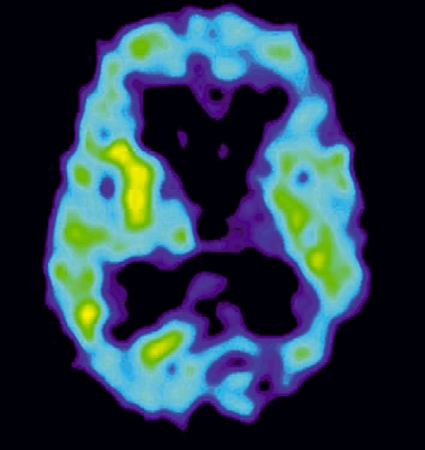

De övriga tillstånden kännetecknas av varierande grad av självmedvetenhet sammanhängande med olika patofysiologisk bakgrund (Figur 1). Minimalt responsivt tillstånd antas återspegla en lägre grad av dekortikering än vegetativa tillstånd, medan akinetisk mutism och paramediant diencefalt syndrom kan orsakas av skador på frontala neuronala nätverk respektive delar av talamus [4].

Prognosen för de olika grupperna är skiftande samtidigt som det finns ökande evidens för effekterna av olika specifika behandlingsstrategier, inklusive farmakologiska. Några av tillstånden kan dessutom avlösa varandra i tiden, vilket är av betydelse i relation till prognosbedömning och planering av behandling (Figur 2). För samtliga grupper gäller att risken för medicinska komplikationer är hög, omvårdnadsbehovet stort och att anhörigkretsen är hårt drabbad. Det finns således behov av kvalificerad både medicinsk, psykosocial och etisk kompetens under det tidiga omhändertagandet [5, 6].